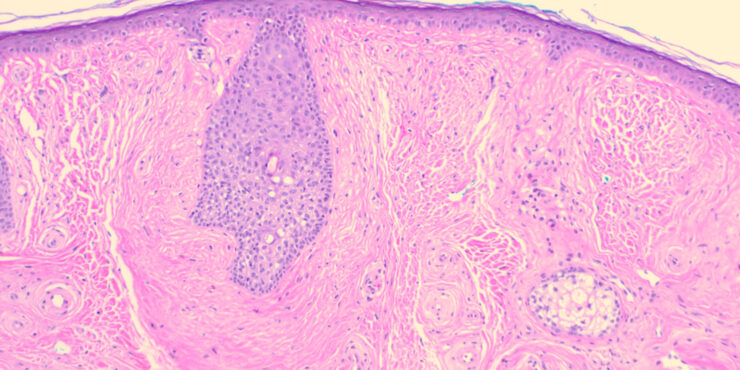

Parapsoriasis Large-plaque = نظير الصدف كبير اللويحات Parapsoriasis There are three entities described as parapsoriasis: small-plaque parapsoriasis, large-plaque parapsoriasis, and parapsoriasis variegata. Large-plaque parapsoriasis and parapsoriasis variegata are best considered as early stages of cutaneous T-cell lymphoma/mycosis fungoides. The small-plaque parapsoriasis is also known as xanthoerythrodermia perstans of Crocker and as digitate dermatosis . Pink-to-yellow, slightly scaly, oval or elongated, […]